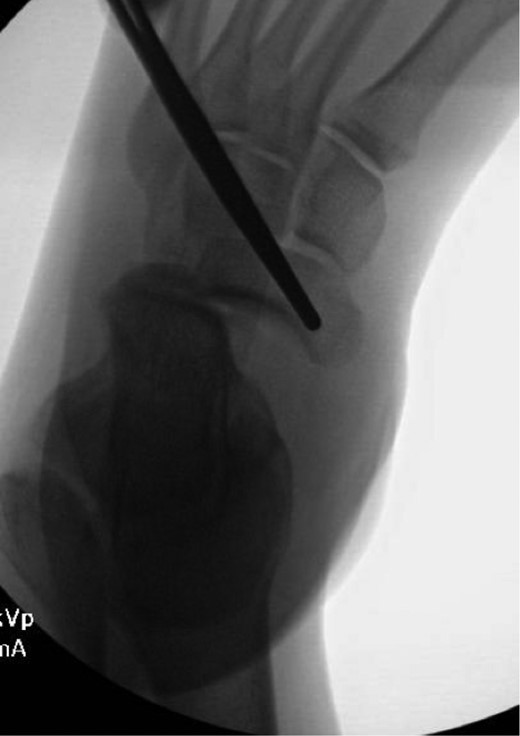

This patient is a 30-year-old male who presented to our emergency room following a head-on motor vehicle accident as a restrained driver. He described pain in his right ankle immediately after the accident and was taken to the emergency department as a trauma alert. ATLS protocol was instituted but no other injuries were identified. The patient’s right ankle was grossly deformed and locked in supination but skin was intact (Fig. 1). The right lower extremity was neurovascularly intact. Initial X-rays (Fig. 2) of the right ankle demonstrated a medial subtalar dislocation without associated fractures. In the emergency department, closed reduction was attempted under conscious sedation but was unsuccessful. Therefore, risks, benefits and alternatives were discussed and the patient elected to proceed with urgent closed vs open reduction of the right subtalar joint and any other indicated procedures.

Once general anesthesia was induced, closed reduction was attempted using axial traction with the knee in flexion. Closed reduction was unsuccessful once again (Fig. 3) so the decision was made to attempt open reduction. An anteromedial approach was used dissect down to the talonavicular joint. Retractors were placed with care to avoid injury to tibialis anterior tendon or superficial peroneal nerve. The joint capsule was seen to be disrupted and further exposure revealed a thin, coronal fracture of the anteromedial aspect of the talar head measuring roughly 2 cm in length and 6 mm in thickness (Fig. 4). Once this fragment was removed, the subtalar and talonavicular joints were easily reduced. It was thought that this incarcerated fragment was the likely cause for the unsuccessful closed reduction. The talar head fragment was unamendable for stabilization due to its small size with poor healing potential, thus it was removed. The talonavicular joint was then percutaneously pinned in retrograde fashion with three K-wires (Fig. 5) to maintain anatomic reduction of the subtalar and talonavicular joints and the foot was splinted. At 2 weeks follow-up the patient was doing well and radiographs revealed no interval loss of reduction (Fig. 6).

Intraoperative AP view localizing the medial subtalar dislocation.